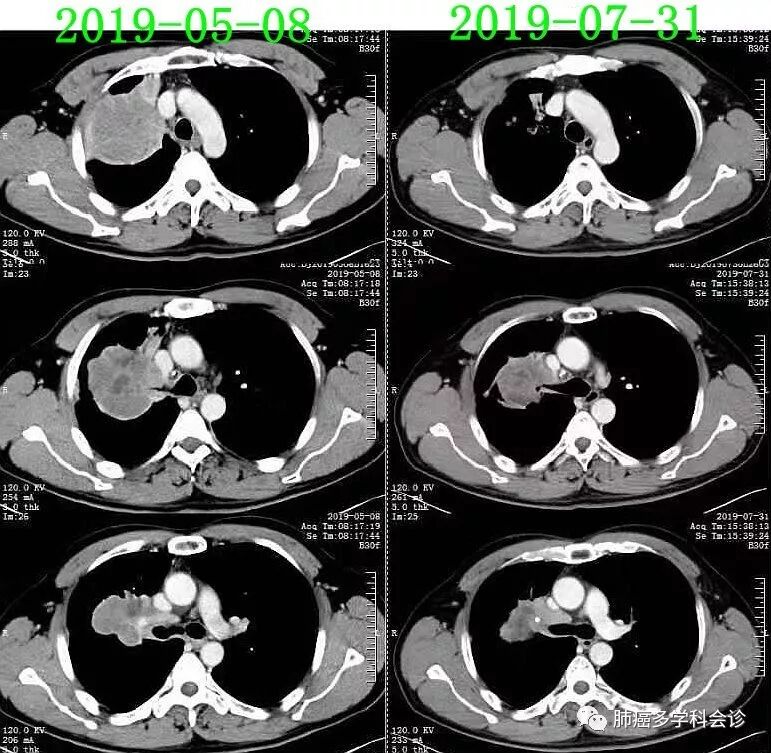

免疫治疗+抗血管生成治疗:

2019.7.31(治疗2个周期后32天)复查CT,肿瘤明显退缩,疗效评价:PR。